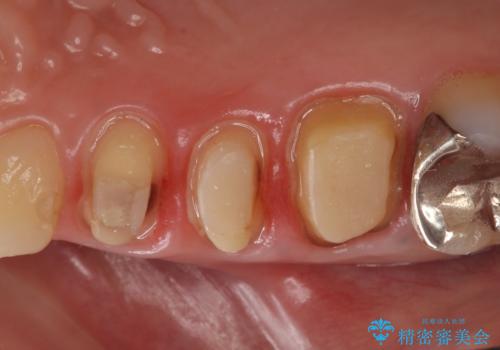

- ものを咬むと右上の歯が痛むといらっしゃった方の症例です。

検査の結果右上5の歯の神経が死んでいたため、根管治療を行った後に、オールセラミッククラウンによる補綴を行いました。

また右上6に関しては再根管治療を行い、右上4に関しては虫歯治療を行った後に、オールセラミッククラウンによる補綴を行いました。